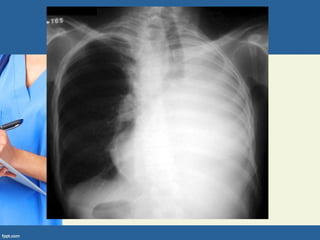

RADIOGRAFIA DO TÓRAX

• As alterações pulmonares não são demonstradas em até

15% dos casos. As principais alterações são:

• Opacidades parenquimatosas: frequentemente unifocais e

predominantemente no pulmão direito, acometendo os lobos

superiores na infância e os lobos médio e inferior em adultos.

Opacidades arredondadas persistentes, medindo até 3 cm de

diâmetro (tuberculomas) são manifestações não habituais

(descritas em até 10% dos casos).

• Linfonodomegalia: observada na maioria das crianças e em até

40% dos adultos. Habitualmente é unilateral, podendo ser bilateral

em até 30% dos casos. As regiões mais comprometidas são a

região hilar e a paratraqueal direita. Frequentemente está

associada com opacidades parenquimatosas e atelectasia

segmentar ou lobar.

Métodos de Diagnóstico

• Atelectasia: decorre da compressão

extrínseca das vias aéreas por

linfonodomegalias.

• Padrão miliar: pequenas opacidades nodulares

medindo 1-3 mm de diâmetro e distribuídas de

forma simétrica, podendo ser assimétrica em

até 15% dos casos. Pode haver associação

com opacidades parenquimatosas.

Derrame pleural: considerado uma

manifestação tardia da TB primária,

ocorre em 25% dos casos.